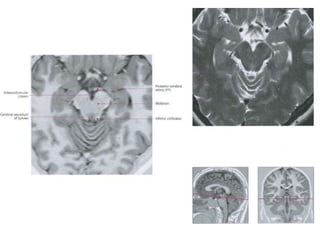

Axial oblique 0.8-mm-thick SSFP MR image

shows the nerve (small arrows) where it

emerges from the interpeduncular cistern

(large arrow), which lies medial to the

cerebellar peduncle (p)

Coronal 0.8-mm-thick SSFP MR image shows

the oculomotor nerve (white arrow) in cross

section between the posterior cerebral artery

(white arrowhead) and the superior cerebellar

artery (black arrowhead), which are distal

branches of the basilar artery (black arrow).

Axial oblique 0.8-mm-thickSSFP MR image shows the nerve (small arrows) where it emerges from the interpeduncular cistern (large arrow), which lies medial to the cerebellar peduncle (p) Coronal 0.8-mm-thick SSFP MR image shows the oculomotor nerve (white arrow) in cross section between the posterior cerebral artery (white arrowhead) and the superior cerebellar artery (black arrowhead), which are distal branches of the basilar artery (black arrow).